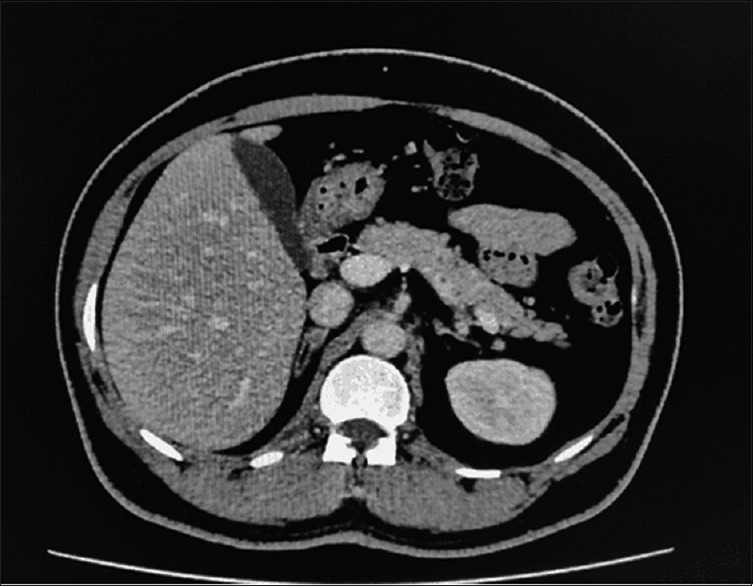

Conn's syndrome or primary aldosteronism (PA) due to aldosterone-producing adrenal adenoma (APA) is the most frequent cause of hypokalemia and secondary hypertension. We are reporting a Primary Aldosteronism(PA) case in an indian male, who presented with recurrent lower limb weakness & was admitted twice for management of his symptoms. On evaluating, laboratory reports revealed that his symptoms are due to refractory severe hypokalemia, metabolic alkalosis, raised serum aldosterone levels, and low plasma renin activity. Transtubular potassium gradient (TTKG) was suggestive of ongoing renal potassium loss. Computed Tomography (CT) angiography of adrenal glands during his first admission showed an 8-mm nodule in the right adrenal gland. CT angiography during his second admission with more severe similar complaints revealed an increase in the size of this nodule. The patient was managed with serum potassium correction and surgical intervention. He underwent laparoscopic right adrenalectomy. Following the surgery, the patient serum potassium normalized and he had a good clinical outcome. We suggest clinicians to consider screening for PA and offer surgical intervention wherever necessary in cases with refractory hypokalemia and secondary hypertension.